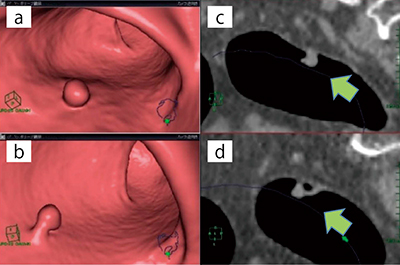

図2は,41歳,男性,検診の便潜血陽性に対し大腸スクリーニング目的で施行した症例である。肛門より12.6cmの直腸に,4.8mm×4.3mm,CT値33.1HUの隆起性病変が認められる(図2 a)。2体位同時観察のVEでは茎の存在(図2 b)と病変部の可動性を認め,Ip病変と鑑別できる。MPR サジタル画像(図2 c,d)でも,その様子は明瞭である。VEの活用で小病変を拾い上げ,その形状,性質を指摘できた一例である。

図2 2体位同時観察画面

a:VE,仰臥位

b:VE,腹臥位

c:MPR,サジタル画像(仰臥位)

d:MPR,サジタル画像(腹臥位)